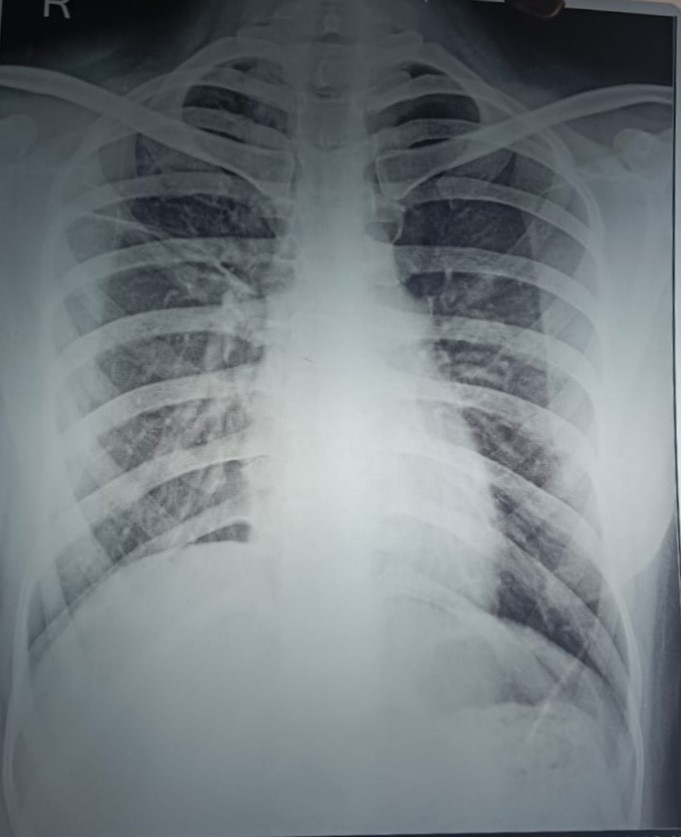

| 118 | IGGMC, Nagpur, Nagpur | P2 | 29-4354 | Mohmad Zahir | Consent taken on Paper | 48 Yrs. |

Provisional Diag : ?

Final Diag : ? |

Result awaited (Suspected TB/Non-TB) | Bilateral (Right Upper Zone & Mid zone, Left lower zone, Mid zone & Upper zone) Old Heald Fibrocalcific Opacity | Abnormality visible on x-ray |